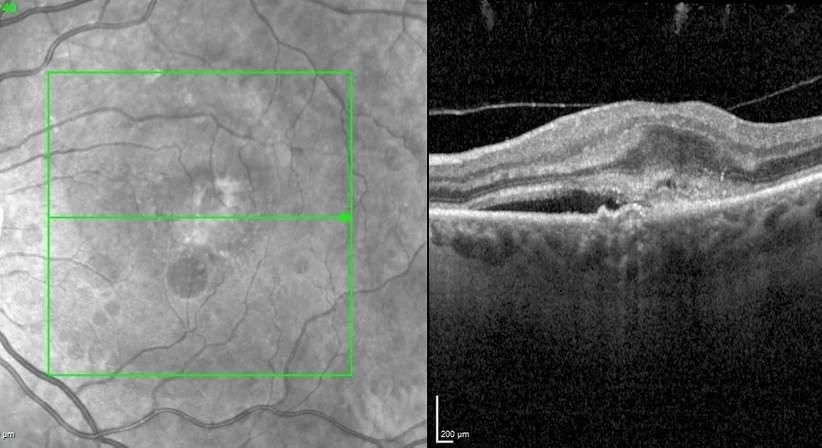

Erkrankungen der Makula kann der Augenarzt mittels eines Mikroskops (sog. Funduskopie) und unterstützend mittels einer hochauflösenden Laser-Schichtbildaufnahme (sog. OCT, optische Kohärenz Tomographie) des Netzhautgewebes diagnostizieren, beurteilen und kontrollieren. Vor allem bei Diabetikern und Patienten mit altersbedingten Netzhauterkrankungen (z.B. altersbedingte Makuladegeneration oder feuchte AMD) sollten regelmäßige Kontrollen der Netzhaut durchgeführt werden. Wir bieten unseren Patienten auch zur Vorsorge hochauflösende OCT-Untersuchungen der Makula an.